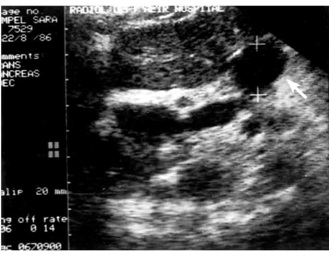

2.על-שמע (אולטרהסאונד) — בחולים הלוקים בשאתות בלבלב אפשר להדגים את השאת, וכן לראות את דרכי המרה (תצלום 23.9).

האולטרה-סאונד האנדוסקופי (EUS) מאפשרת לראות את השאת, את גודלה (איור 24.9);

האם פרצה לאיברים אחרים, תפסה כלי דם או מערבת בלוטות לימפה (תצלום 25.9).